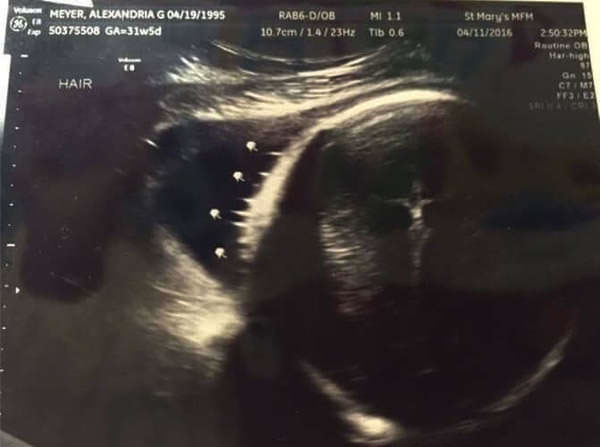

ಎಲ್ಲಾ ಅಮ್ಮಂದಿರು ತಮ್ಮ ಮಕ್ಕಳನ್ನ ದೇವರ ವರ ಎಂದು ಭಾವಿಸುತ್ತಾರೆ. ಆದರೆ ಕೆಲ್ಲಿ ಎಂಬಾಕೆಯ ಈ ಅಲ್ಟ್ರಾಸೌಂಡ್ ಸ್ಕ್ಯಾನ್ ಫೋಟೋದಲ್ಲಿ ಮಗುವಿನ ಹಣೆಯ ಮೇಲೆ ಒಂದು ಏಂಜಲ್ ಅಥವಾ ದೇವದೂತನು ಕಣ್ಣಿಟ್ಟು ನೋಡುತ್ತಿರುವುದನ್ನ ಕಾಣಬಹುದು.